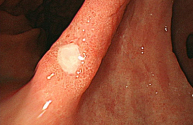

정상 위의 내시경 사진